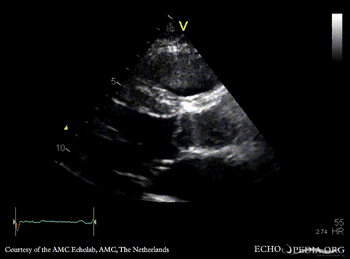

Davids procedure

Courtesy of: AMC Echolab, AMC, The Netherlands

PLAX: native aortic valve and prosthesis in ascending aorta PLAX with Color Doppler